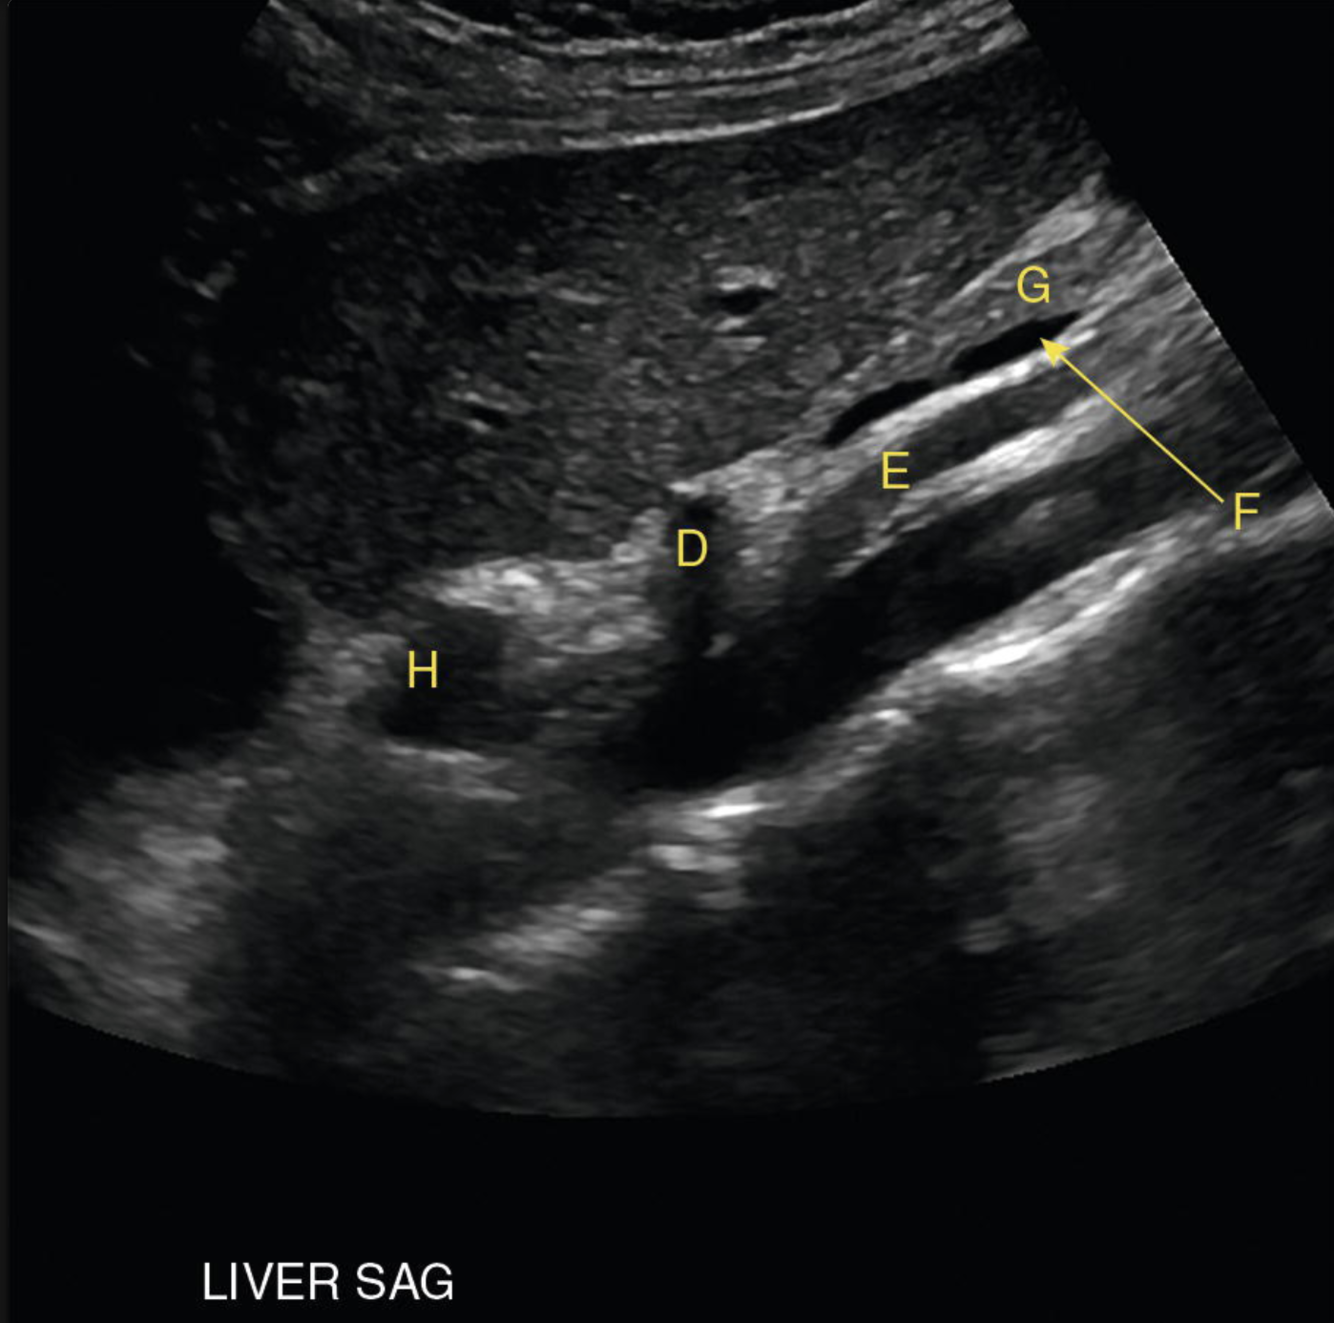

Identify the following structures:

D: celiac a.

E: SMA

F: splenic v.

G: pancreas

H: distal esophagus

Most common cause of this?

“Double duct” sign = pancreatic adenocarcinoma at the pancreatic head.